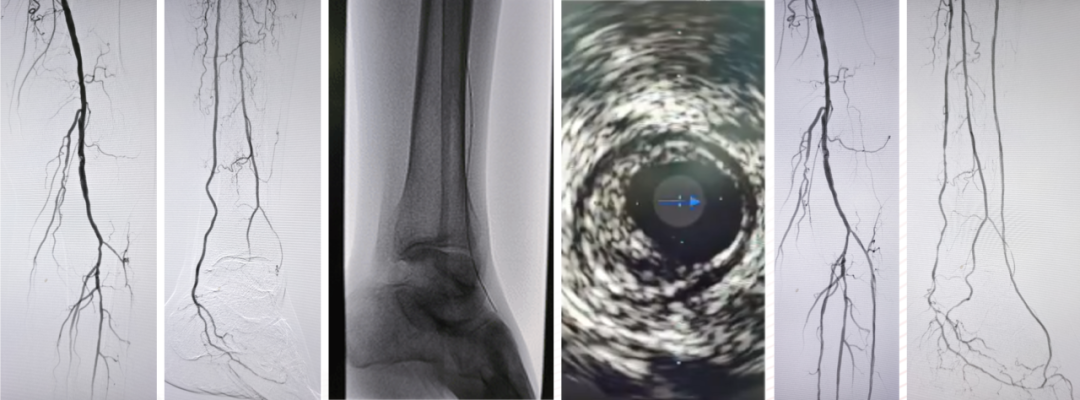

Case 3:一例腘动脉闭塞患者,胫前动脉远端不显影,足底动脉仅通过侧支隐约可见。术者选择顺穿足底动脉,导丝经足弓上行,成功进入胫前动脉真腔,建立轨道后完成球囊扩张,恢复足弓血流,术后1个月患者溃疡愈合。

★ 逆穿足底动脉建立轨道

Case 4:另一例膝下三支闭塞,仅腓动脉远端通过侧支供应足底。正向开通腓动脉后,胫后及胫前仍无法进入真腔,遂穿刺足底动脉,将导丝逆行送至踝部,与正向导丝会师后完成扩张,最终开通足底动脉。

Case 5:正向导丝经胫前进入,逆向导丝经足底上行,在踝部无法汇合。先后扩张正向球囊和逆向球囊后,导丝顺利进入同一腔道,成功开通足弓。

Case 6:采用双球囊对吻技术:正向使用外周球囊,逆向使用冠脉球囊,在6F鞘内同时扩张2mm重叠段,导丝顺利通过。